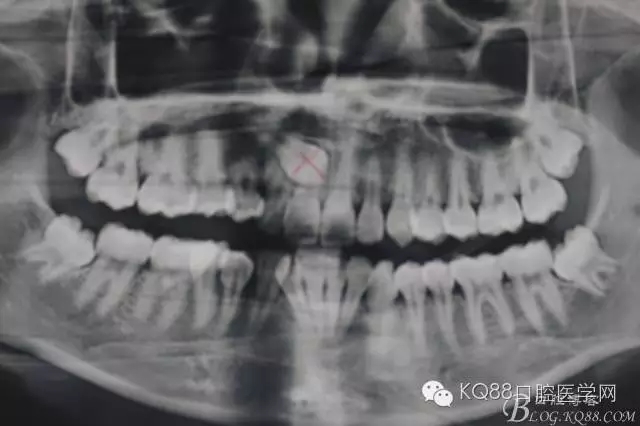

病例資料一:(腭側(cè)埋伏阻生尖牙的拔除)

患者、魯xx、女、主訴:右側(cè)上腭不適,要求診治。??茩z查:14輕度近中扭轉(zhuǎn),遠(yuǎn)中鄰面齲壞。13未見萌出。12與14有鄰接、腭側(cè)可見輕度隆起。全景片檢查:13埋伏阻生、13牙冠位于11與12之間。正畸科會(huì)診建議拔除14、正畸牽引13到正常位置?;颊卟豢紤]正畸治療。與患者溝通,建議拔除13,患者同意拔除,簽知情同意書。

圖1.患者術(shù)前的全景片影像檢查:13位于11、12之間。全景片無法得知13到底在唇側(cè)還是腭側(cè)。